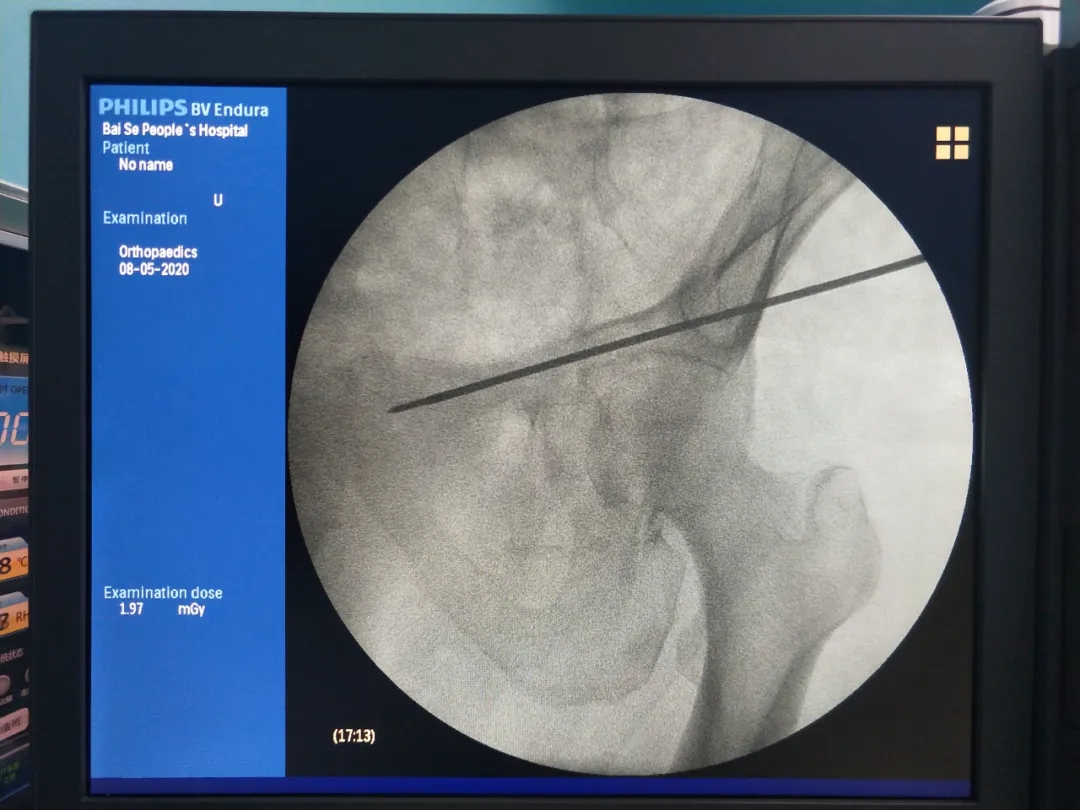

开展天玑?骨科手术机械人辅助下早期股骨头坏死病灶扫除植骨术。。。。。。天玑?骨科手术机械人系统收罗图像后,,,,,,设计导针偏向和位置,,,,,,按设计一次性精准的将导针置入妄想位置,,,,,,将坏死区刮除彻底,,,,,,然后用人工骨和自体骨充分填充坏死区,,,,,,增进局部愈合,,,,,,延缓股骨头坏死希望,,,,,,尽可能阻止髋枢纽置换,,,,,,也真正体现了“精准微创”的治疗理念。。。。。。

术中刮除坏死组织